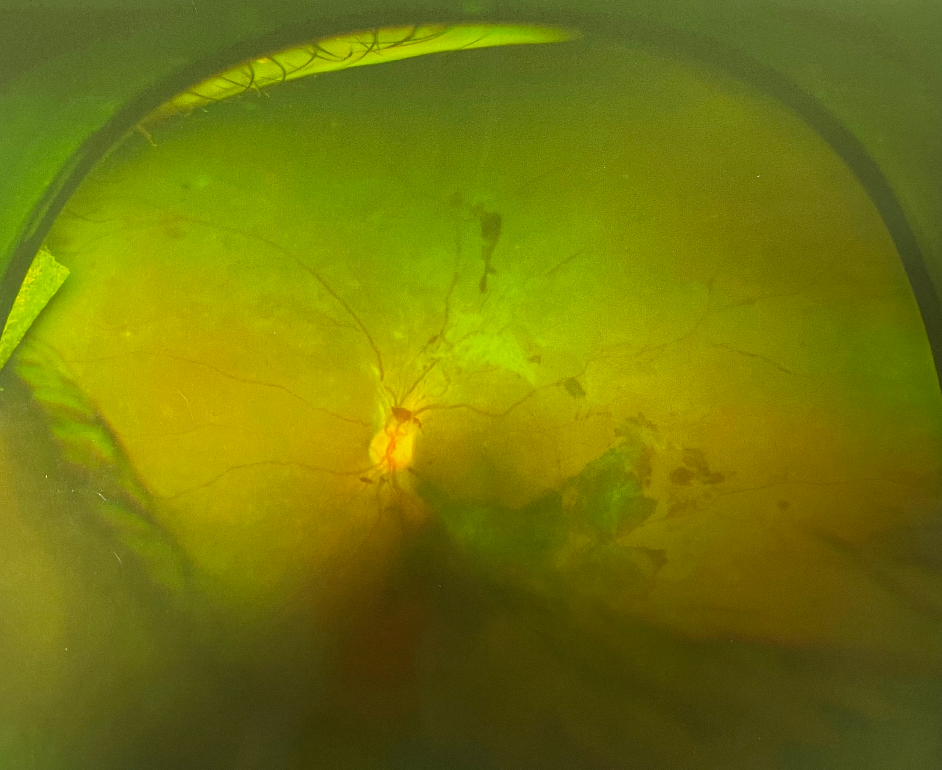

眼底出血并不是一種獨(dú)立的眼病,且出血的原因復(fù)雜,對(duì)視力的影響也很大。如果不及時(shí)加以改善和控制,還有可能引起黃斑病變、青光眼等許多嚴(yán)重并發(fā)癥,甚至是失明。很多人沒有出現(xiàn)眼底出血的情況,因而對(duì)其不甚了解。那么眼睛眼底出血原因有哪些?今天就和大家一起了解下眼睛眼底出血原因。

老年性黃斑變性引起的眼底出血部位一般限于黃斑變性,好發(fā)于50歲以上的老年人。主要表現(xiàn)為突然視力下降,到了病情晚期,還會(huì)出現(xiàn)大面積視網(wǎng)膜下出血、玻璃體出血,對(duì)視力的損傷極大

眼睛眼底出血原因2、視網(wǎng)膜靜脈阻塞

如果患者有高血壓、動(dòng)脈硬化的病史,在出現(xiàn)視網(wǎng)膜靜脈分支堵塞時(shí)就有可能出現(xiàn)視力突然下降、視網(wǎng)膜水腫和滲出。若是視網(wǎng)膜指定脈堵塞或視網(wǎng)膜中央靜脈堵塞,患者在眼底出血的同時(shí)還可能伴有明顯的視力下降

眼睛眼底出血原因3、糖尿病視網(wǎng)膜病變

當(dāng)糖尿病患者發(fā)生時(shí)視網(wǎng)膜病時(shí)便會(huì)出現(xiàn)眼底出血。在病癥初期,大都表現(xiàn)為少量點(diǎn)狀出血,并伴有微血管瘤。隨著病情的發(fā)展,患者的眼睛可能會(huì)有點(diǎn)狀的出血和滲出,有的患者還會(huì)有黃斑病變及視力下降的癥狀。因此糖尿病患者一定要按時(shí)按量的服用藥物,只有將糖尿病的癥狀控制了才能有效控制眼底出血這一情況。

眼睛眼底出血原因4、其他原因

除了上述的這三種病癥,炎癥性疾病、免疫復(fù)合物侵犯血管壁時(shí)、全身性血管病和血液病分也可引起高血壓視網(wǎng)膜病變和糖尿病性視網(wǎng)膜病變,從而導(dǎo)致眼底出血,比如高血壓視盤血管炎等。